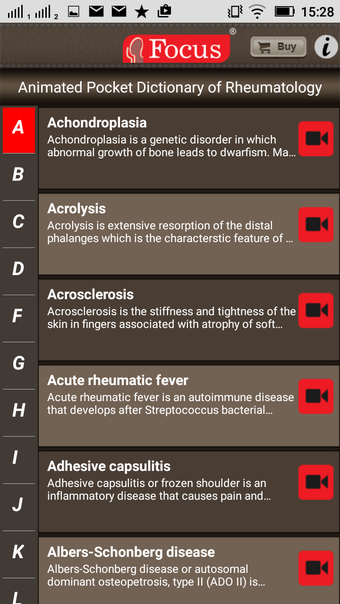

该应用程序是一本包含100个与风湿病相关的术语和定义的词典。定义以简单易用的格式呈现,辅以3D动画和视频。该应用程序分为两个部分:第一部分与医疗状况有关,第二部分与治疗和用于治疗状况的药物有关。

该应用程序是一本包含100个与风湿病相关的术语和定义的词典。定义以简单易用的格式呈现,辅以3D动画和视频。该应用程序分为两个部分:第一部分与医疗状况有关,第二部分与治疗和用于治疗状况的药物有关。